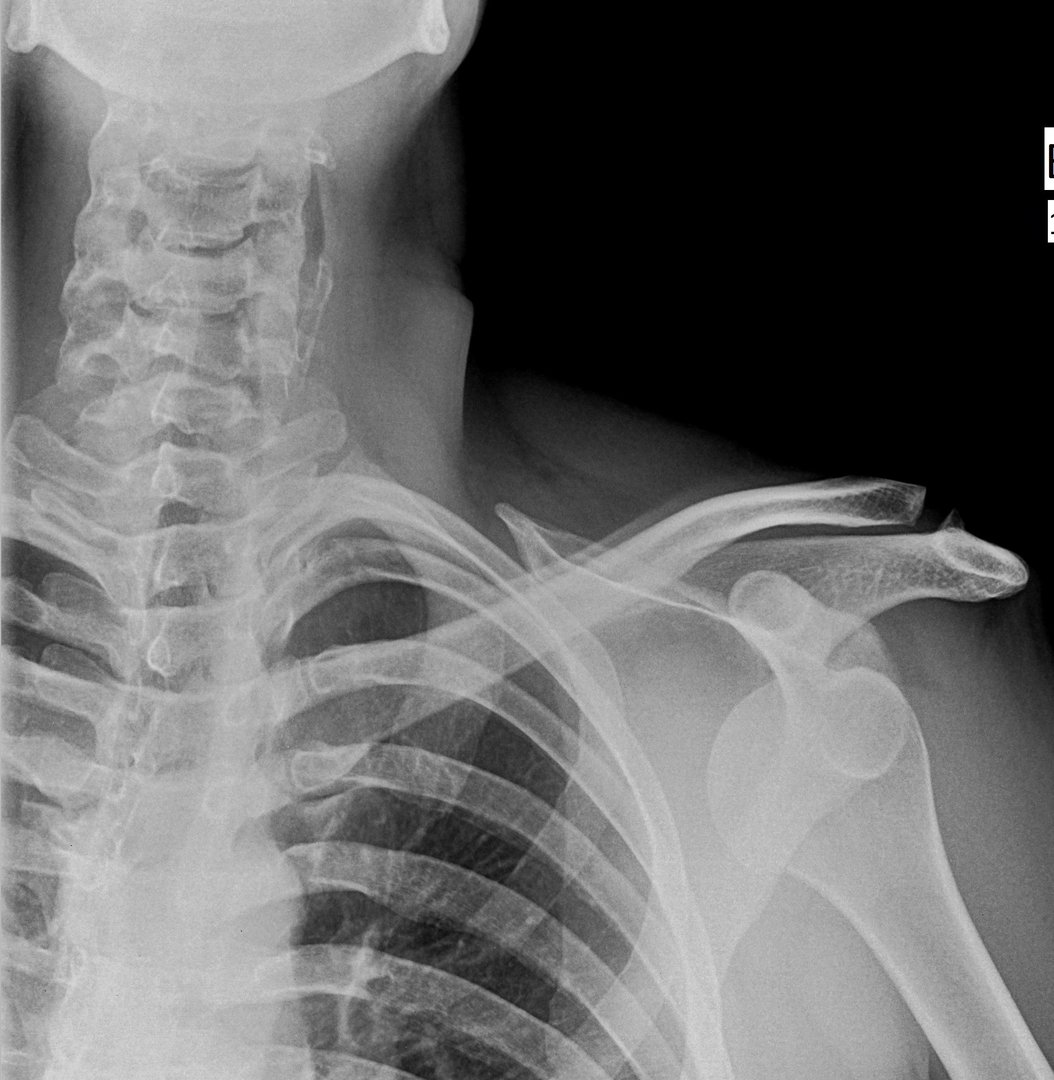

x ray shoulder radiograph show shoulder dislocation

X-Rays

Essential to confirm dislocation direction, identify bone injuries, and rule out fractures before reduction.